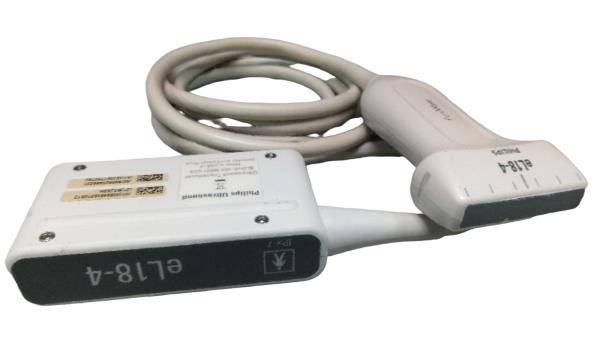

Connectors: 2 probe connectors